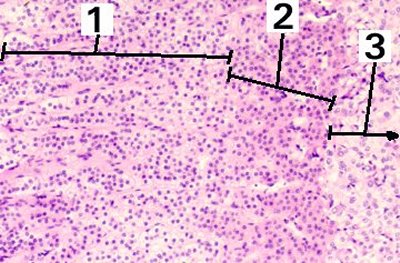

This is an enlargement of the deeper part of the cortex of the adrenal gland.

Fig 56-003 1. Zona fasciculata

2. Zona reticularis

3. Medulla